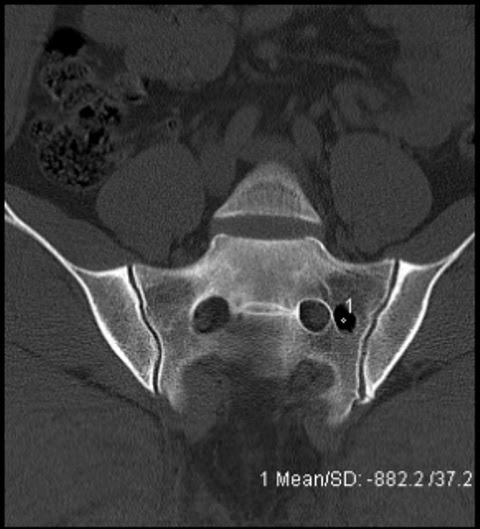

Intraosseous Pneumatocysts.

Случай 2: Внутрикостная пневмоцистика

Внутрикостная пневмоцистика